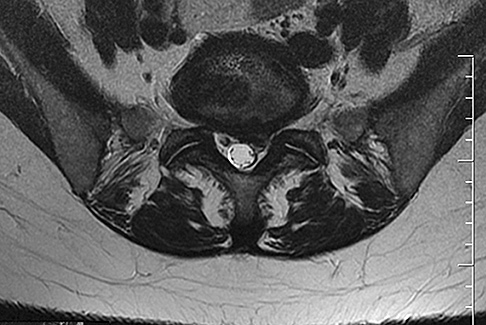

Preoperative MRI images are shown from a 67-year-old woman with neck pain, bilateral upper extremity paresthesias, progressively worsening balance, several falls, and increasing problems in both hands with dropping objects. Figure 1 is a sagittal view, Figure 2 is an axial cut at C2-3, Figure 3 is an axial cut at C5-6, and Figure 4 is an axial cut at C6-7. The patient’s motor strength is grade 4+ of 5 in the bilateral upper extremities.

What is the best next step?

4. Posterior decompression and fusion Discussion: D

The patient has degenerative changes with central and foraminal stenosis from C2-7, including spinal cord compression at C2-3, C5-6, and C6-7. Her progressively worsening balance, falls, and clumsiness are consistent with cervical spondylotic myelopathy. Given the progressive nature of the neurologic symptoms, surgery is recommended for patients with worsening

symptoms. Physical therapy potentially could provide pain relief but would not address the spinal cord compression. Cervical epidural steroid injection is not recommended because of the increased neurologic risk in the setting of substantial spinal cord compression. Given the multiple levels involved and the extension to the C2-3 level, an anterior approach would increase the risk of morbidity and pseudarthrosis compared with the posterior approach, which would allow adequate decompression of the central and foraminal stenosis.

Surgery for cervical myelopathy is performed to decompress the spinal cord, stabilize the spine, and prevent further neurologic injury. Most patients obtain considerable pain relief and some improvement in balance and clumsiness, depending on the severity of the symptoms. Complete resolution of all symptoms should not be expected.